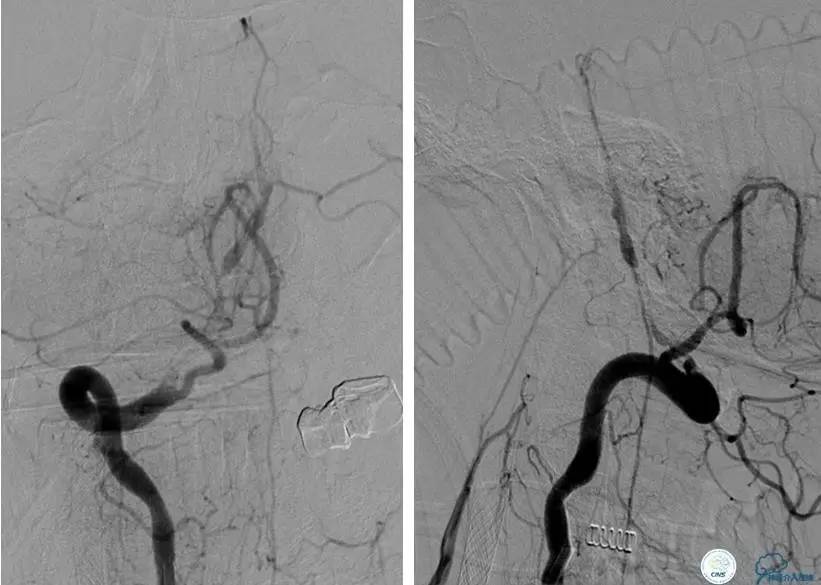

患者:58岁男性,反复头晕、肢体无力3月,当地造影见多发颅内动脉狭窄、闭塞,转来我院。

▼首先行颈动脉CTO开通术,手术顺利,Wallstent支架。

▼1周后行右侧椎动脉V4段CTO开通术。

▼微导丝穿过狭窄段,微导管造影,小球囊预扩张,2mm。

▼根据血管情况选择较大球囊再次预扩张。

▼置入2枚Wingspan支架,手术成功。

▼术后即刻CT,梗死灶内再灌注出血。

患者无症状,中性治疗。4月21日电话随访,一般情况好,当地CT示出血吸收期。